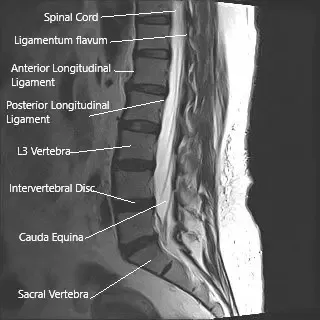

La médula espinal transmite mensajes entre el cerebro y el cuerpo. Recorre la columna vertebral y termina alrededor del nivel de la primera vértebra lumbar. Por debajo de este punto, un haz de nervios continúa hacia abajo dentro del canal espinal; estos se llaman cauda equina porque se asemejan a la cola de un caballo.

Estos nervios controlan la sensibilidad y el movimiento en las piernas, la vejiga, el intestino y los órganos sexuales. Debido a que están expuestos dentro del conducto y no están protegidos por hueso o tejido tan fuertemente como la médula espinal, son más sensibles a la presión o a las lesiones.

Resonancia magnética de la columna lumbar en la sección sagital que muestra la cauda equina (cola de caballo)